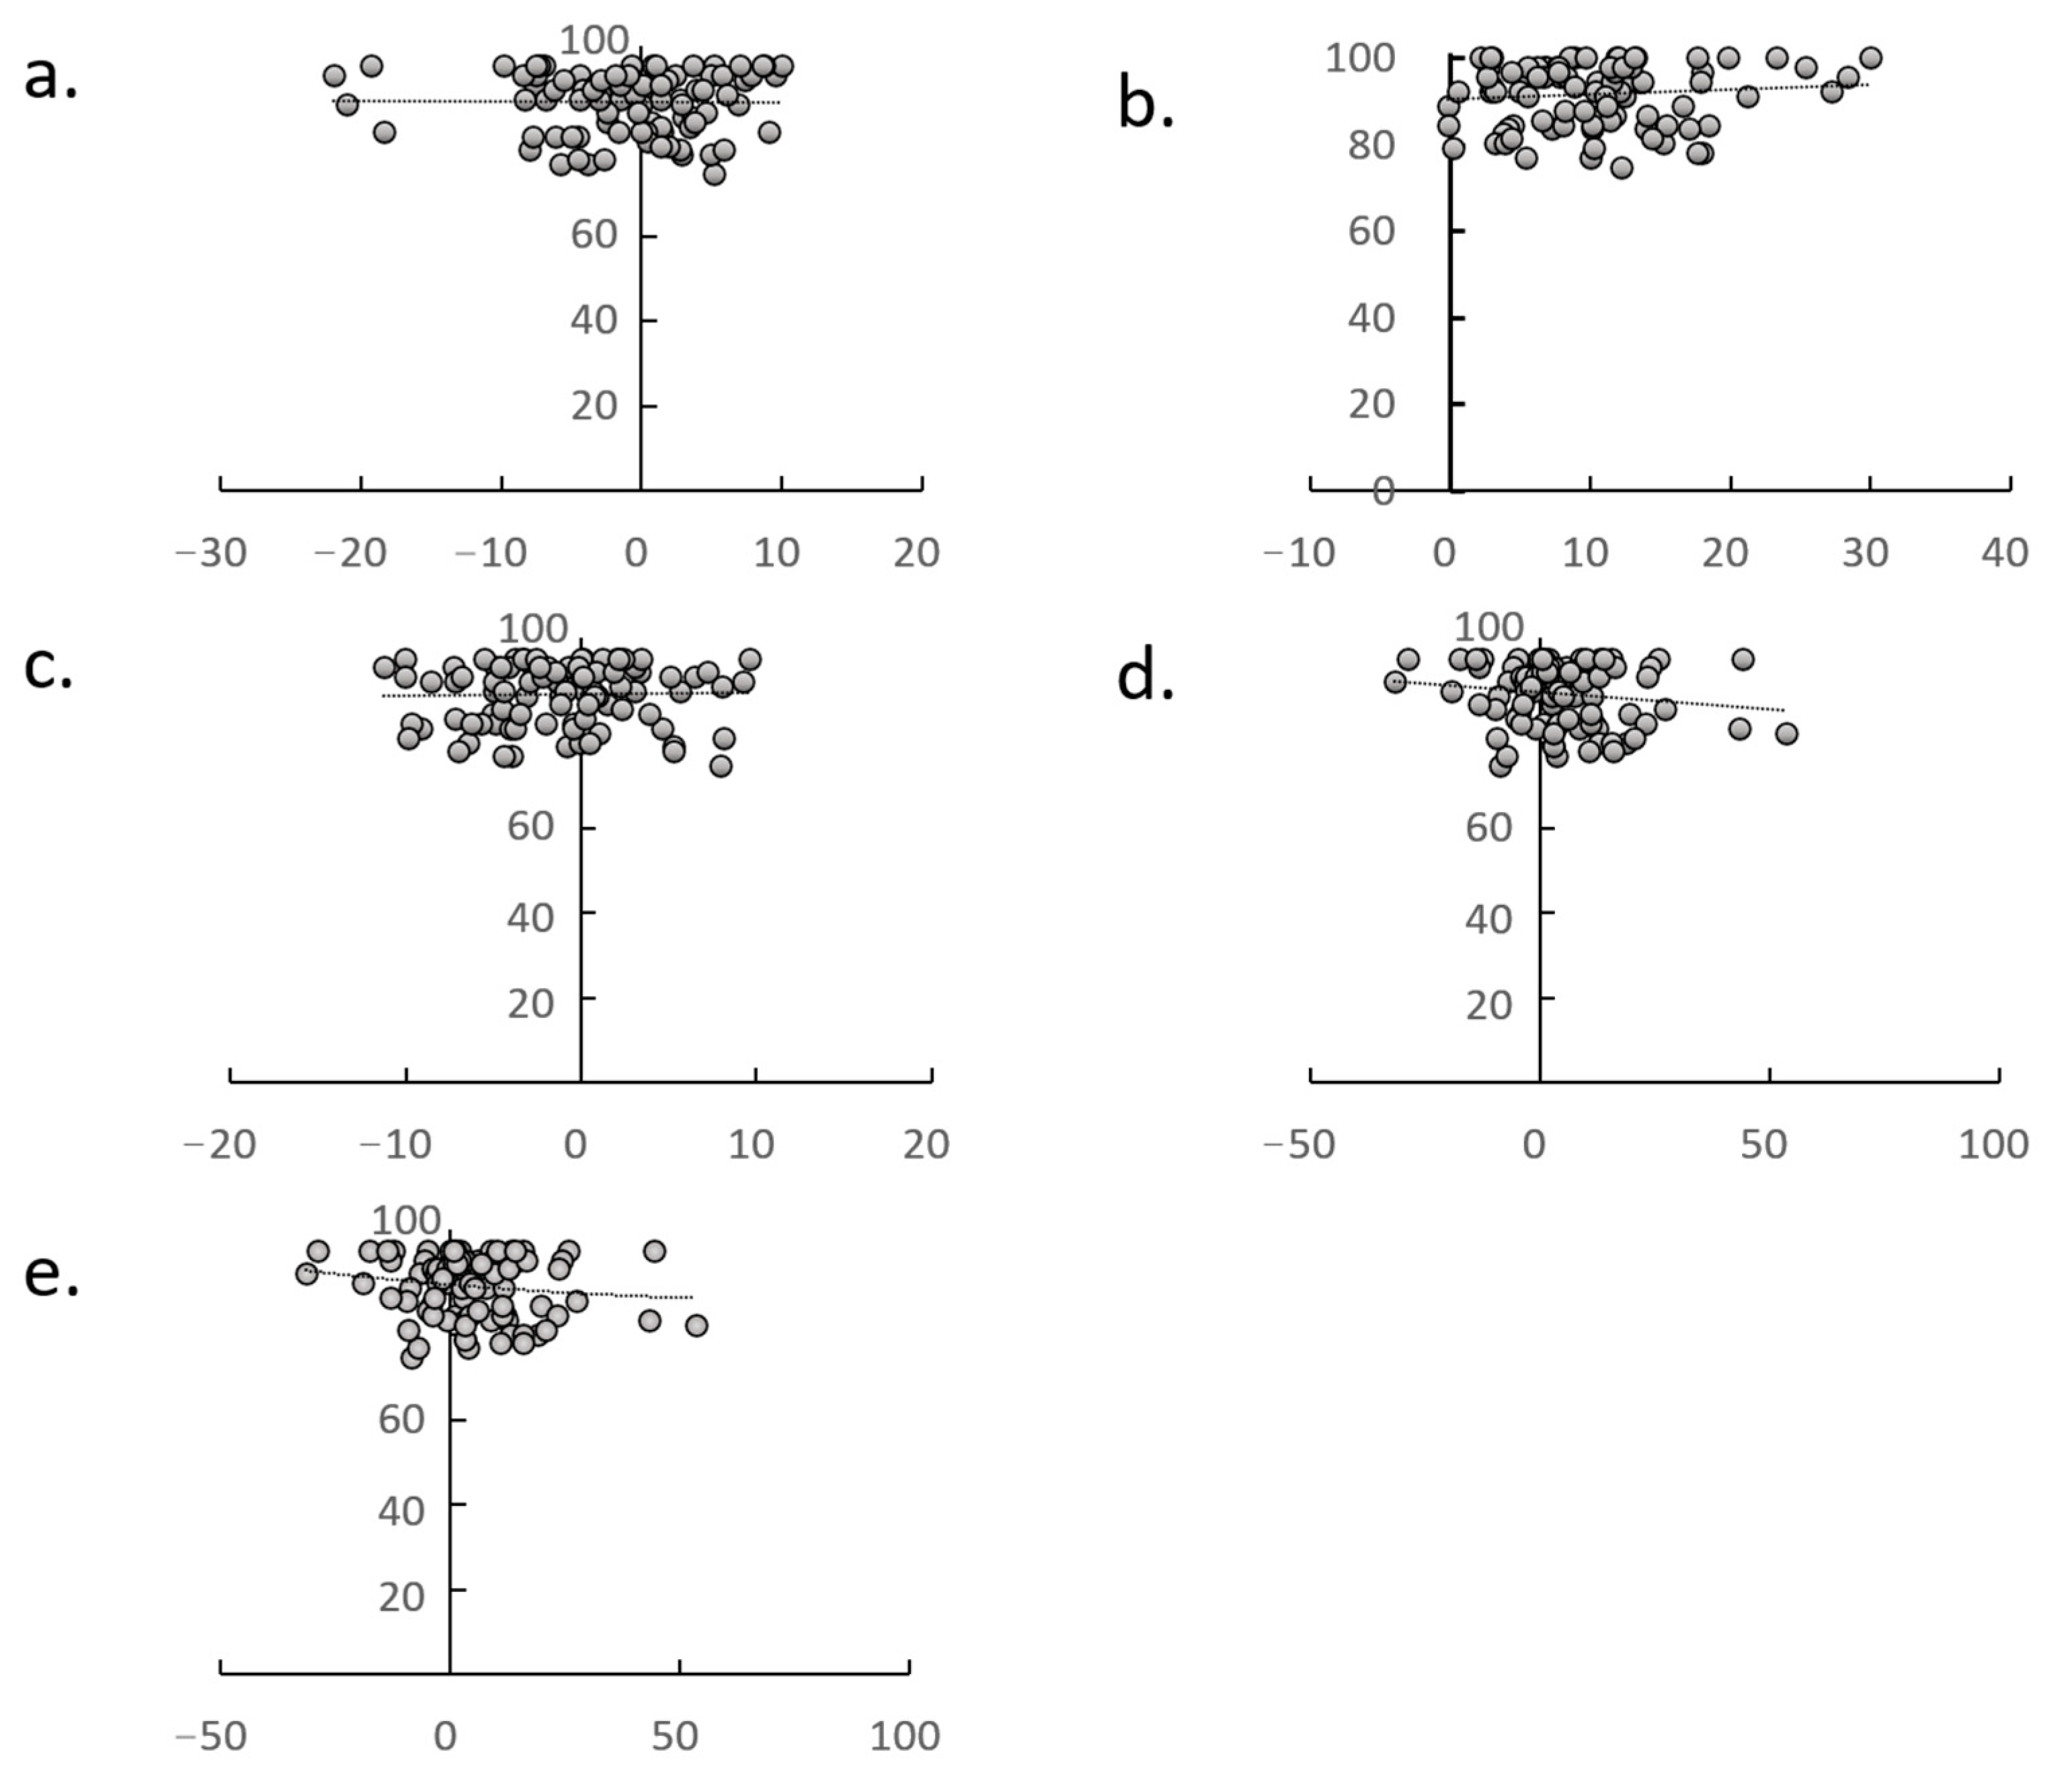

| Formula | Correlation Coefficient | p-Value | |

|---|---|---|---|

| * | y = 0.3355x − 0.8332 | r = 0.317 | 0.008 |

| ** | y = 0.4868x − 0.3424 | r = 0.566 | <0.001 |

| ☨ | y = −0.2712x | r = 0.289 | 0.018 |

| ☨☨ | y = −0.7824x | r = 0.342 | <0.001 |